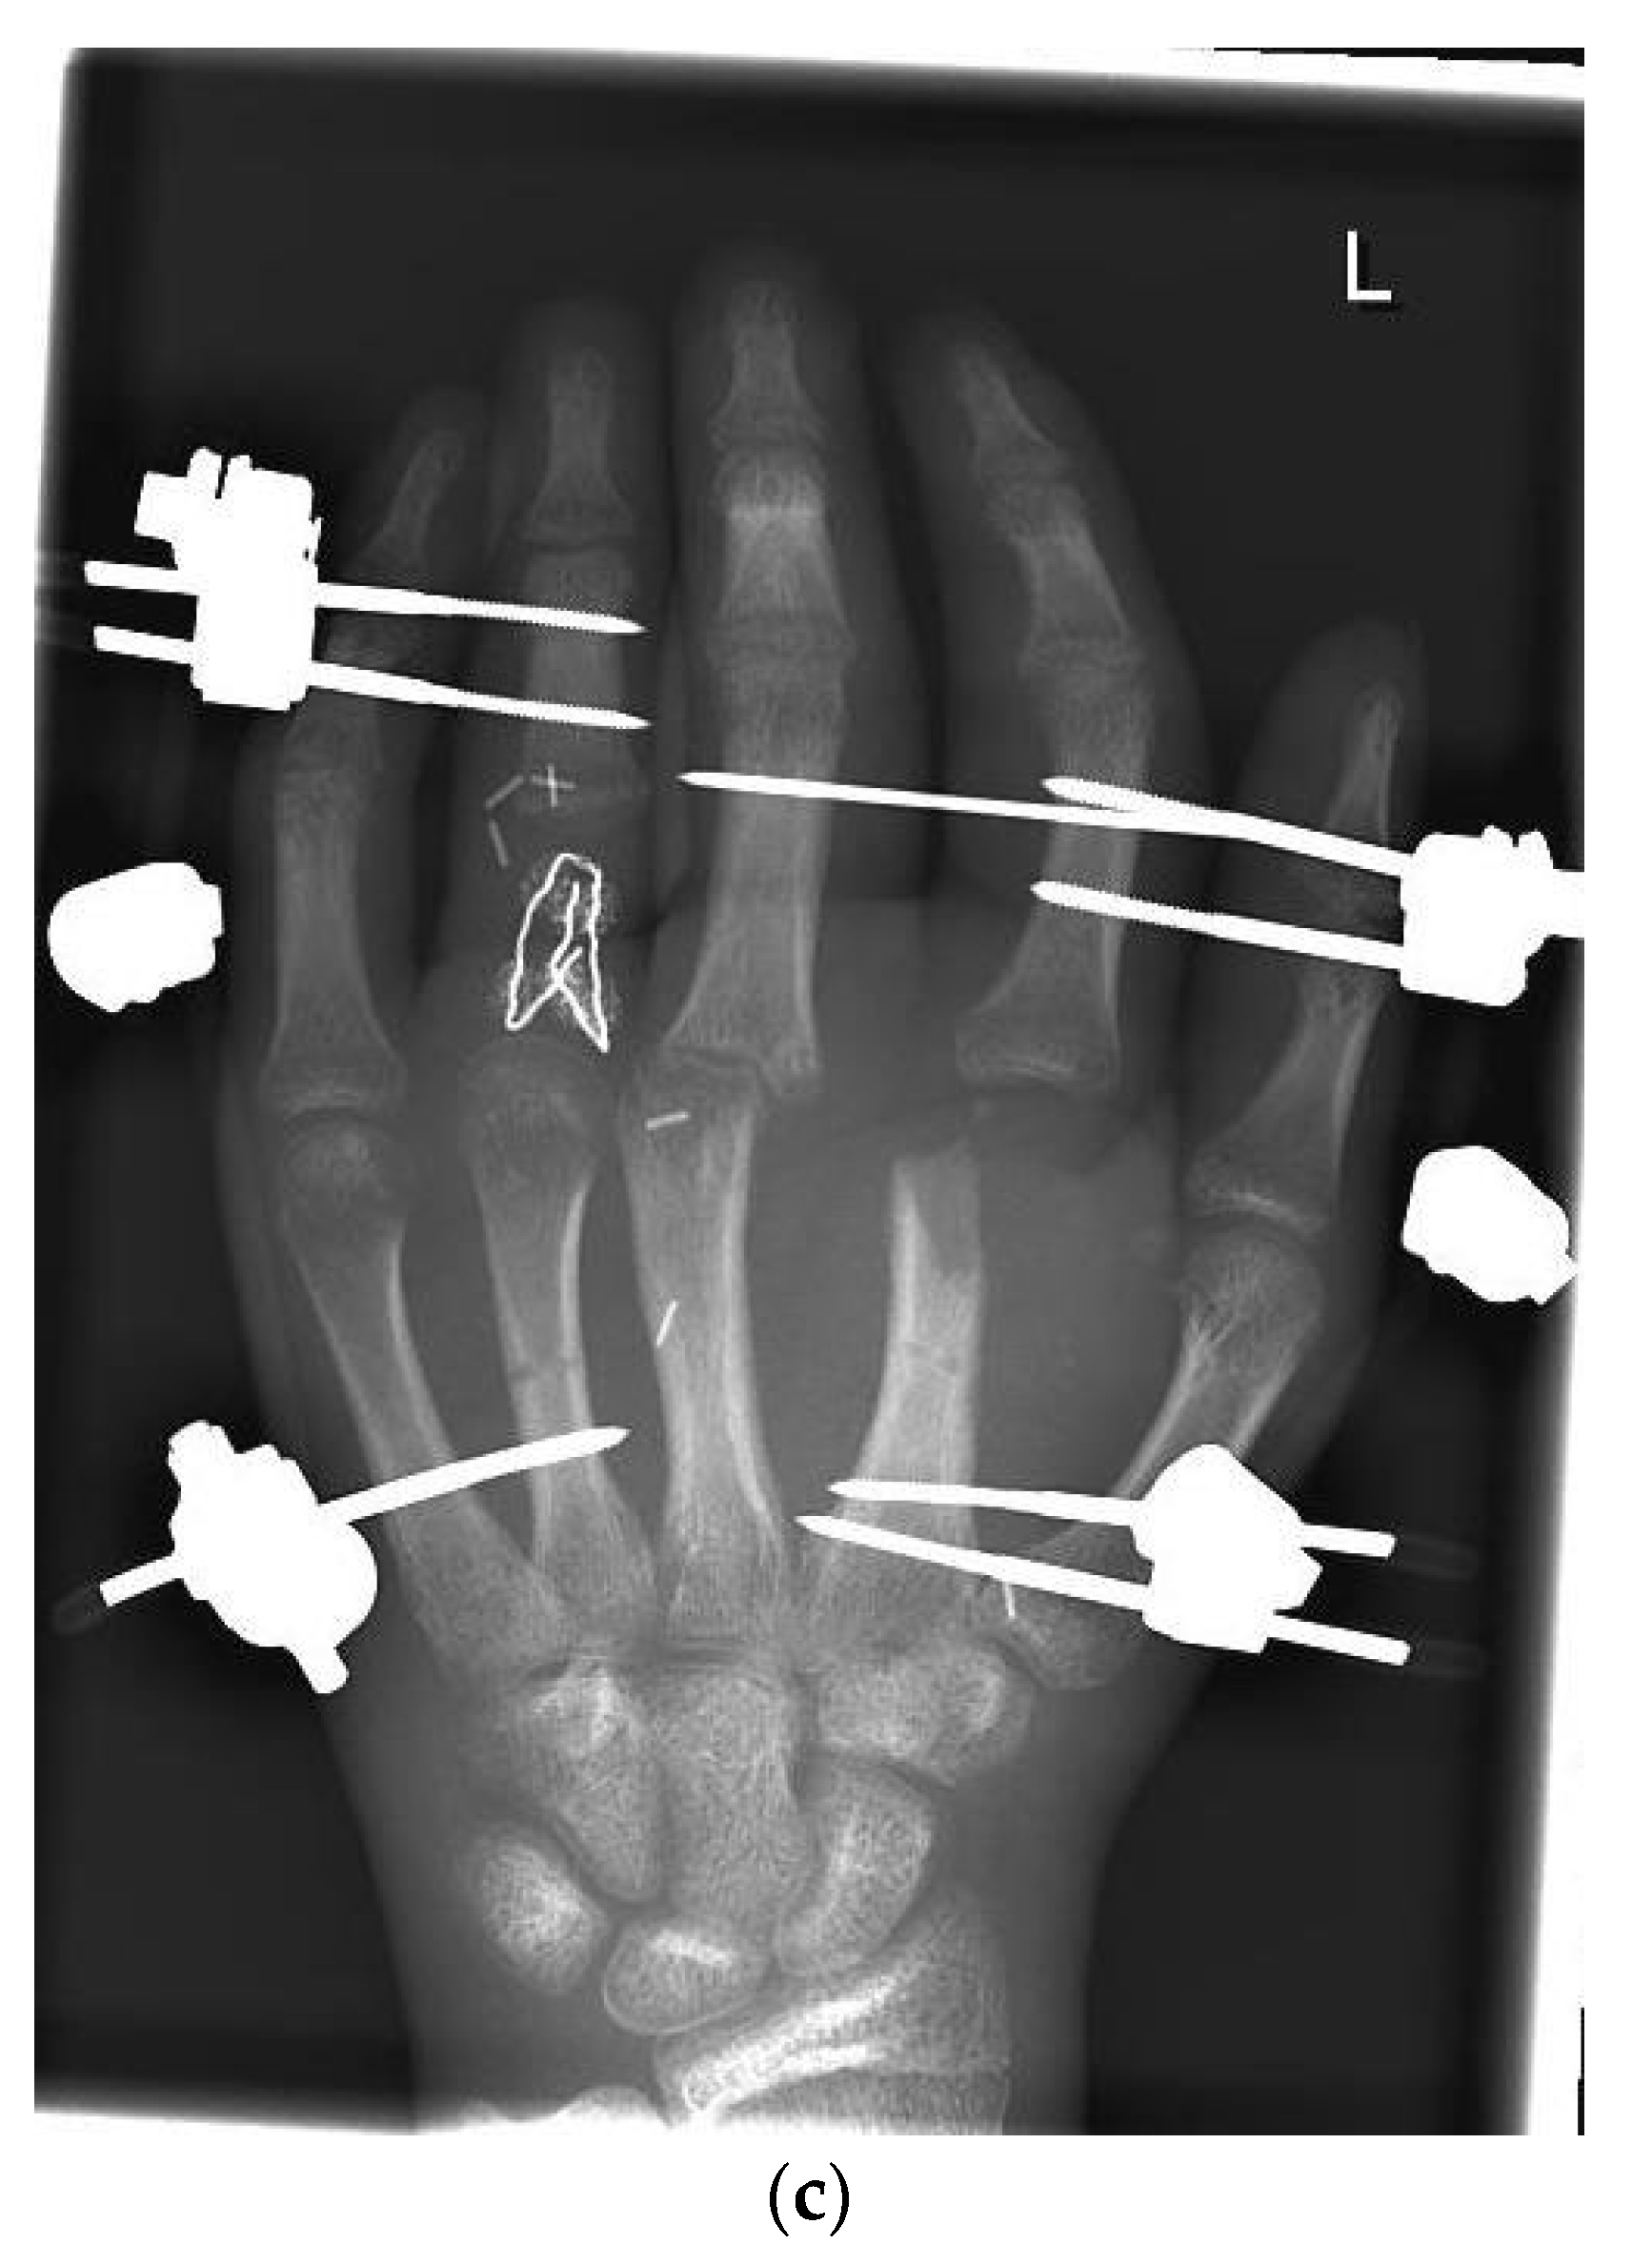

| 1 | 17 | m | Circular saw injury to the dominant left hand with a subtotal amputation of DII–DIV at the level of the MCP joints | Replantation of DIV Amputation of the distal metacarpals DII and DIII, PIP-Joint transfer to DII from the left second toe, MCP endoprosthesis DIII, Free double toe joint transfer to PIP and DIP from the right second toe | Finger-palm distance (FPD) DII–DV 0–0–1–0 cm Fingernail table distance (FNTD) DII–DV 0–0–0–0 cm Kapanji 10/10. DII: MCP 0–0–80°, PIP 0–0–100°, DIP 0–0–80°; DIII: MCP 0–0–80°, PIP 0–0–100°, DIP 0–0–50°; DIV: MCP 0–10–90°, PIP 0–0–90°, DIP 0–0–10°; DV: MCP 0–0–90°, PIP 0–0–100°, DIP 0–0–90°. | The two-point discrimination reached 4–6 mm in all fingers. | Pinch left 7 kg, right 10 kg. Force left 8 kg, right 18 kg. |